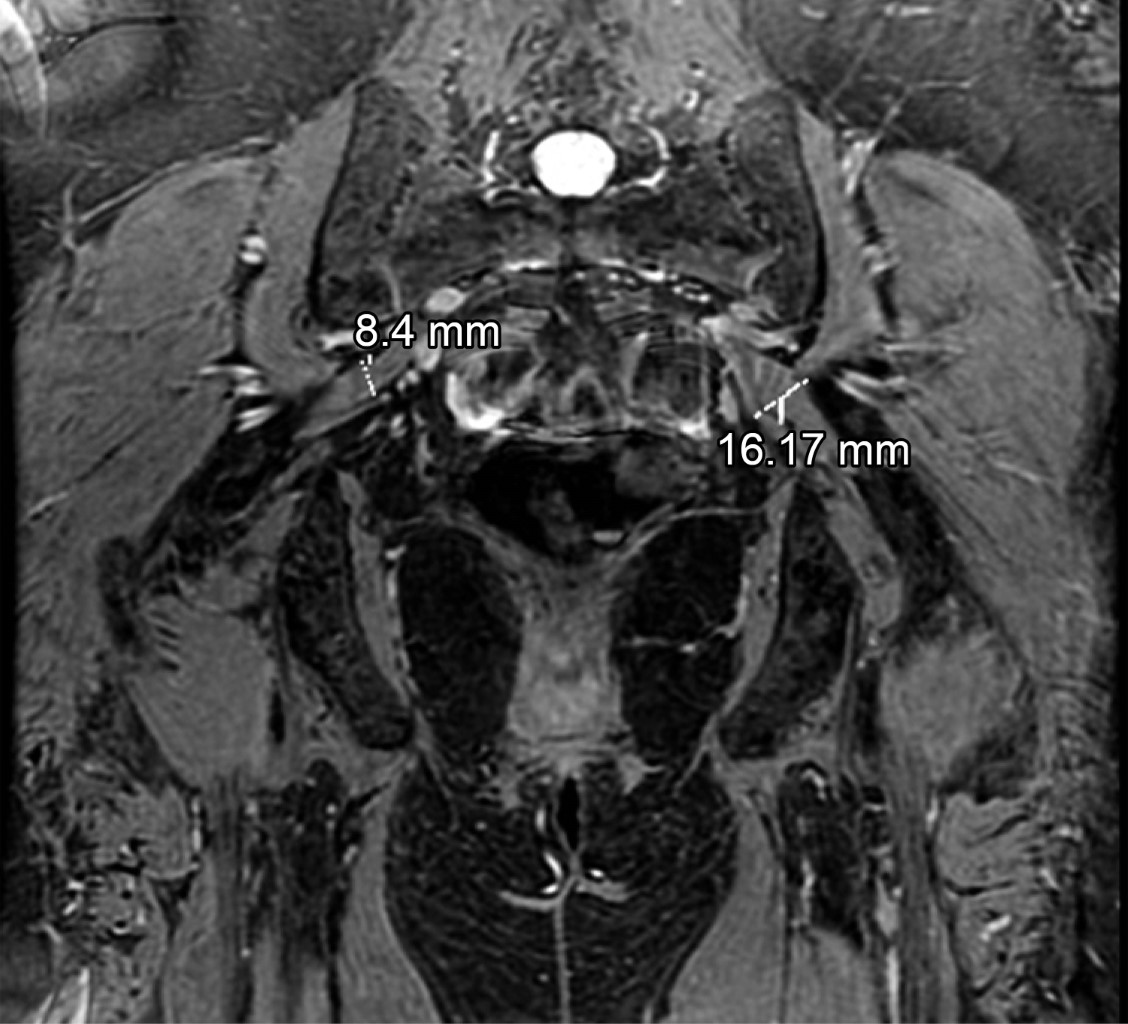

Mujer de 56 años, peso 58 kg, estatura 1.54 m, a quien se le solicitó resonancia magnética del nervio ciático por presentar síntomas de dolor en la pierna izquierda de dos meses de evolución, en estudio previo de resonancia magnética de columna lumbar no se demostró patología discal. En el estudio se identificó asimetría de los músculos piriformes, en las imágenes axiales del lado izquierdo el músculo piriforme mide hasta 12.7 mm de grosor y en el lado derecho 6 mm (Figura 1), en imágenes coronales mide en el lado derecho 8.4 mm y en el lado izquierdo hasta 16 mm (Figura 2), con incremento de la señal del músculo piriforme en el lado izquierdo y datos de compresión del nervio ciático a este nivel. Como otros hallazgos, la paciente presentó cambios de coxartrosis incipiente, bursitis trocantérica bilateral y edema leve por proceso inflamatorio bilateral de los músculos glúteo mayor y medio (Figura 3).

Figura 2